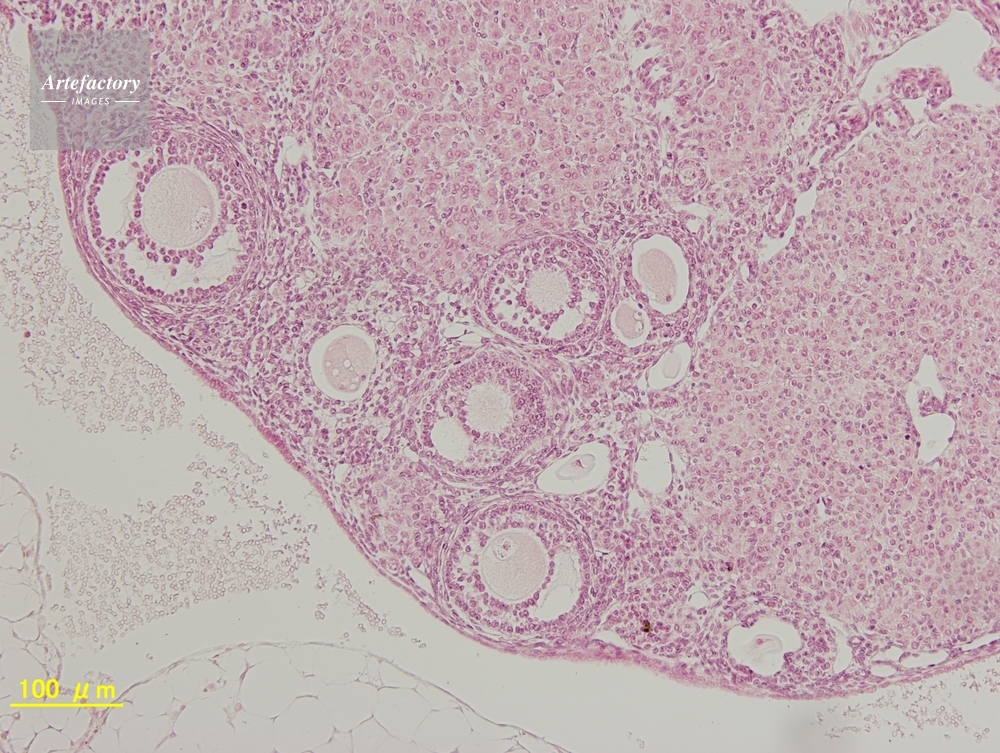

| 作品タイトル | マウス,卵巣 | モデルリリース | なし | |

| 作家 | OLYMPUS CORPORATION Technolab | プロパティリリース | なし | |